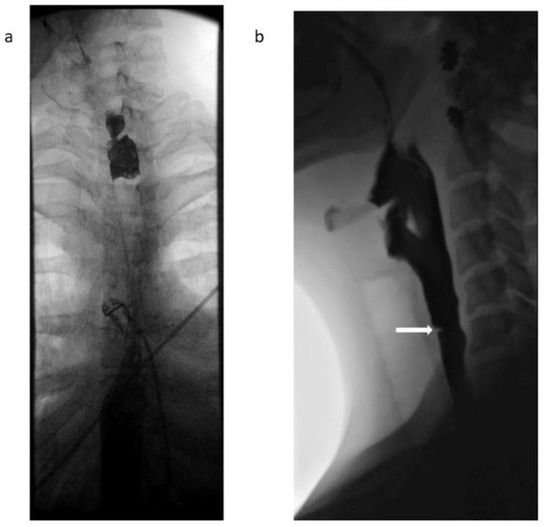

| Patient 2 | Web/stenosis at the cricopharyngeus unable to pass with neonatal scope due to resistance, guideware placed under fluoroscopic guidance and dilation performed with Savary dilator to 8 mm |

| Patient 3 | Two benign appearing intrinsic stenoses were found at the circopharyngeus at 15 cm and 20 cm from the incisors that could not be traversed with the neonatal scope, dilation performed with Savary dilators to 11 mm |